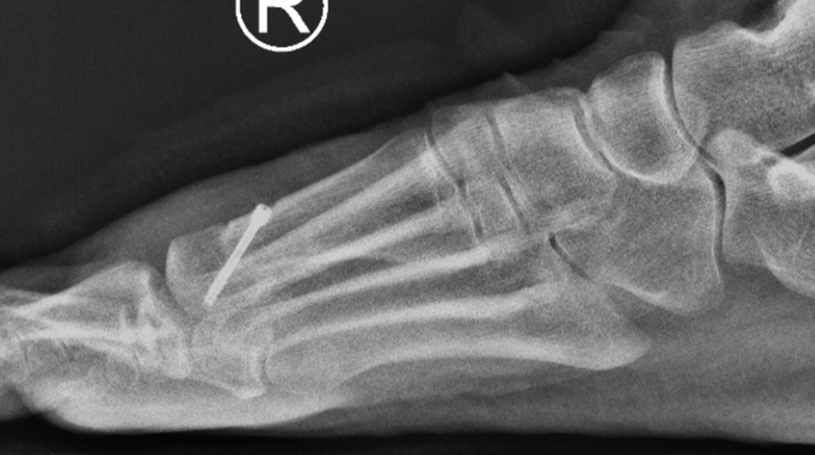

Figure 2: Post op x rays showing the joint remodelled (spurs removed) and the decompression osteotomy/bone cut allowing for improved joint motion